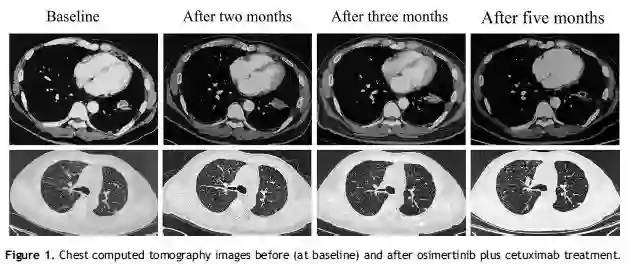

这个病例发表于Journal of Thoracic Oncology   (IF:12.460)。患者为50岁中国男性,不吸烟,肺癌伴多发转移(肝、骨、肾、肾上腺),病理诊断为肺腺癌,基因检测为EGFR 20 ins(A767_S768ins SVD)。确诊后最初给予标准化疗6周期(培美曲塞+卡铂+贝伐珠单抗),随后培美曲塞+贝伐珠单抗维持治疗(2018年2月9日起);治疗之初曾获得PR,但最终出现病情进展。此时患者PS 2分,不宜继续化疗。

受前述基础研究的启发,中山大学肿瘤防治中心的方文峰教授自2018年11月14日起给予该患者奥希替尼 80 mg/d+西妥昔单抗400 mg q2w治疗。治疗的第1月和第2个月 CT检查显示病灶(原发+转移)有轻微缩小,患者一般情况有改善,疗效评价为SD。安全性评价为可耐受(可见II级皮疹等)。此后奥希替尼增量为160mg/d,患者无不适主诉。联合治疗5个月后CT显示左下肺叶病灶明显缩小,评价为PR。目前患者还在继续该联合方案治疗,PFS超过9个月。

这是国际上首次报告三代TKI奥希替尼联合西妥昔单抗对于EGFR 20 ins的NSCLC患者有效,并提示大剂量奥希替尼或可作为耐受良好患者的治疗方案。当然,这一成果还需要进行大型临床试验验证,但无疑给EGFR 20 ins的NSCLC患者的治疗提供了一个极具潜力的新方向。